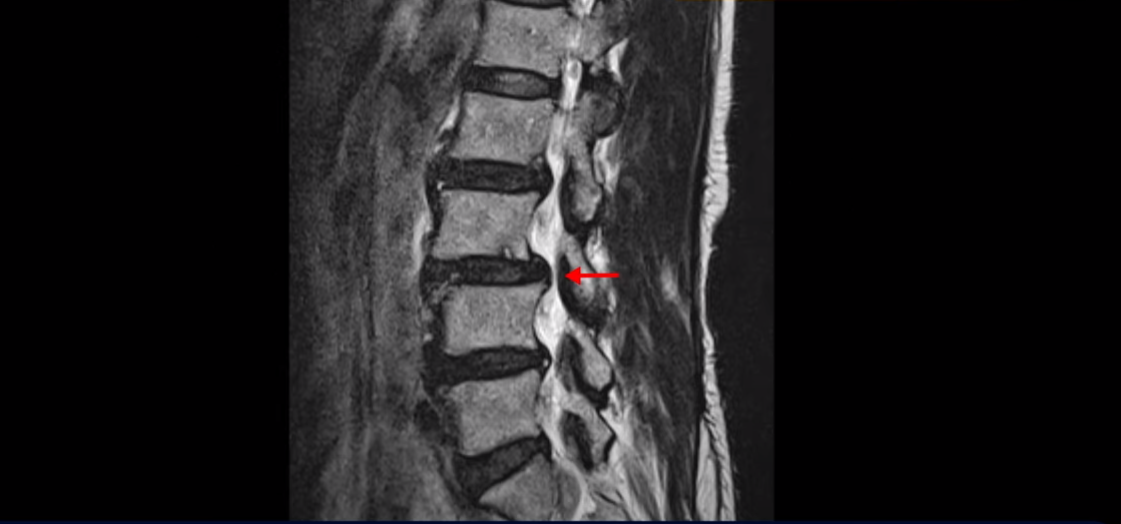

이분 허리를 보면 여러 마디의 퇴행성 디스크와 협착이 있습니다.

2번 3번과 3번 4번은 신경다발이 지나가는 척추관도 좁아져 있습니다.

또 3번 4번에는 척추뼈가 밀려나간 전방전위증도 있습니다.

이분은 정형외과 병원에서 3마디 디스크 파열이라고 수술 권유를 받았는데 저희는 디스크 파열은 잘못된 진단이라고 봅니다. 여러 마디 보이는 디스크 문제는 파열이 아닌 퇴행성디스크들이고 아픈 원인은 전방전위와 협착증 증상입니다. 전방전위와 협착증이긴 하지만 아주 심한 게 아니고 발병한지도 얼마 되지 않아서 근육재활치료를 하면 2주 정도면 빨리 호전될 수 있는 상태였습니다. 왜 이런 환자가 치료하기 훨씬 쉬운 건지, 치료는 어떻게 하는 건지 지금부터 설명 드립니다.

이분이 처음 발병한 건 저희 치료를 시작하기 불과 2주 전입니다. 만일 이분이 아프기 전인 몇 달 전에 MRI를 찍었다면 지금 보시는 MRI와 많이 다를까요? 정답은 전혀 차이가 없다입니다. 뼈가 밀려나가고 신경 구멍이 좁아진 건 이미 오래 전에 벌어진 일입니다. 뼈가 밀려나가고 신경 구멍이 좁아져 있는 채로 아무런 증상을 느끼지 않고 66세까지 잘 산 것입니다. 이런 걸 잠복 협착이라고 합니다. MRI로 협착이 보이지만 아무런 증상이 없다는 뜻입니다.